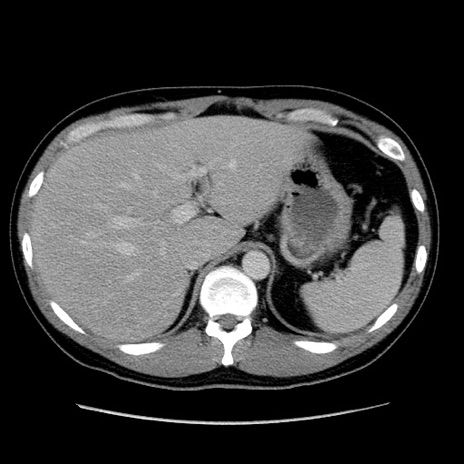

症例4(横断像)

【症例】30歳代男性

【主訴】腹痛、嘔吐

【現病歴】昨晩から突然の腹痛あり、その後嘔吐、軟便も出現。腹痛が改善しないため救急搬送となる。2日前にしめ鯖の食事歴あり。

【身体所見】意識清明、苦悶様、BP 135/90mmHg、BT 35.7℃、腹部:平坦、やや硬、心窩部〜臍部に自発痛、圧痛あり、筋性防御+、反跳痛-

【データ】WBC 8100、CRP 0.57